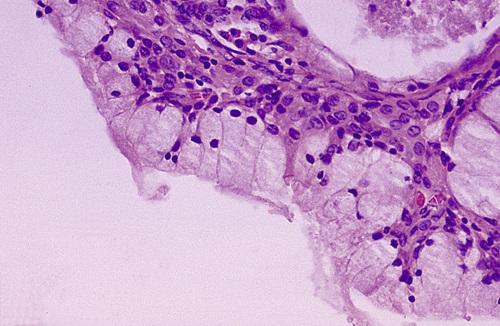

Histopathologic Features

- mucin surrounded by a granulation tissue

- numerous foamy histiocytes (macrophages)

- adjacent glands often contain chronic inflammatory cell infiltrate

Mucin-filled cystlike cavity beneath the mucosal surface. Minor salivary glands are present below and lateral to the spilled mucin.

mucocele

High-power view showing spilled mucin that is associated with granulation tissue containing foamy histiocytes.

mucocele